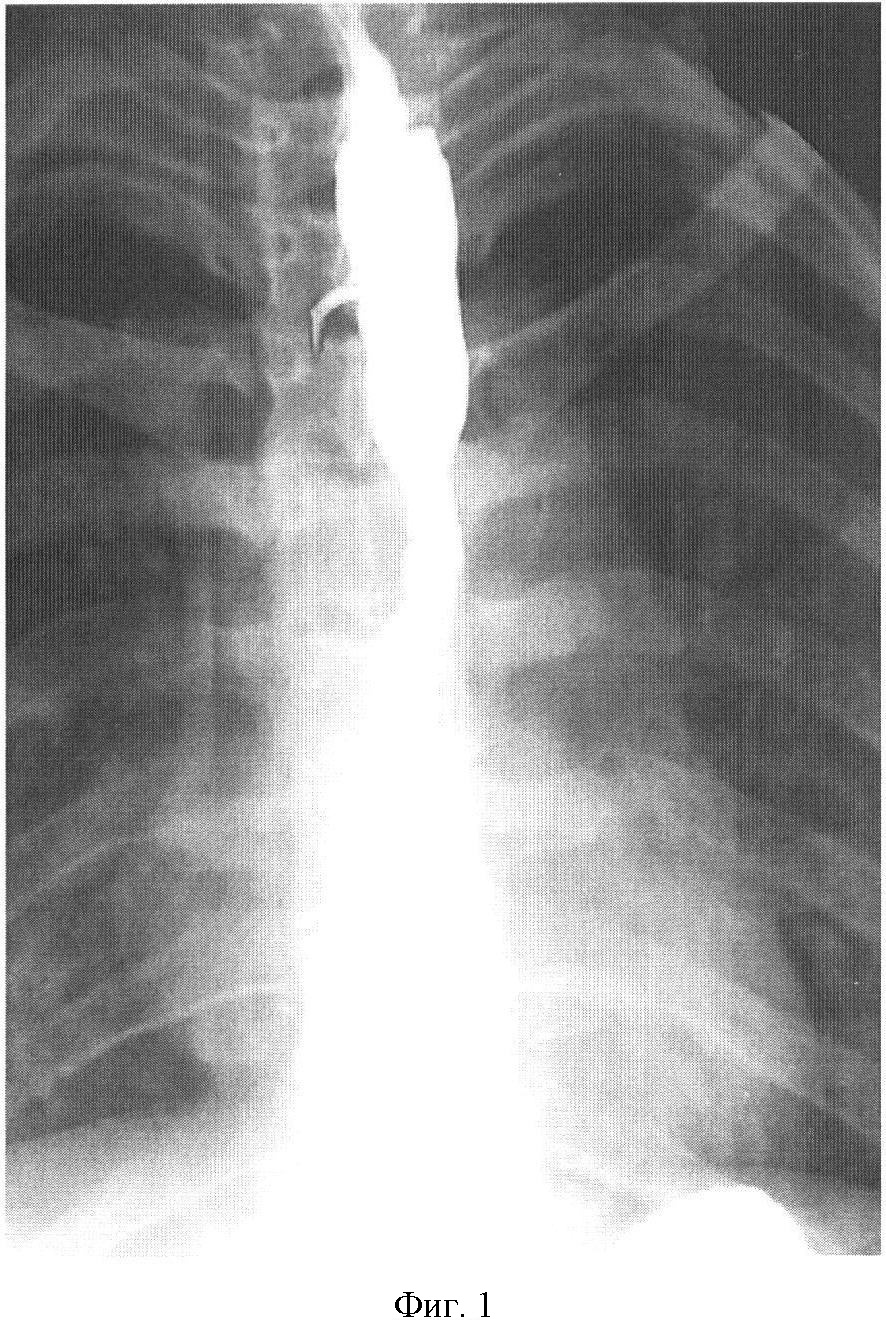

На фиг.1 представлена рентгенограмма пищевода с контрастным веществом: определяется контрастирование трахеопищеводного свища. На фиг.2 представлена эндоскопическая картина просвета пищевода: устье трахеопищеводного свища указано стрелкой. На фиг.3 представлена эндоскопическая картина просвета пищевода: предварительно в устье трахеопищеводного свища, открывающегося в просвете трахеи, было ведено 0,8 мл красящего вещества (метиленовой сини), после этого в просвете пищевода определяется прокрашивание устья трахеопищеводного свища (указано стрелкой). На фиг.4 – пломбирование устья трахеопищеводного свища тахокомбом, предварительно устье свища было последовательно подвергнуто электрокоагуляции и химиокоагуляции (96% этиловый спирт). На фиг.5 – клиппирование запломбированного устья свища. На фиг.6 – контрольная эзофагоскопия, выполненная через 3 месяца после операции: в просвете пищевода в области устья трахеопищеводного свища определяются две скрепки. На фиг.7 – контрольная рентгенограмма после эндоскопического лечения (через 3 месяца): в области трахеопищеводного свища определяется незначительный дефект наполнения (указан стрелкой), трахеопищеводный свищ не контрастируется.

на рентгеноскопии с контрастным веществом определяется трахеопищеводный свищ на уровне Т-1 по правой стенке пищевода до 0,3 см, протяженностью 0,3 см. Контраст попадает в трахею, при кашле полностью эвакуируется;